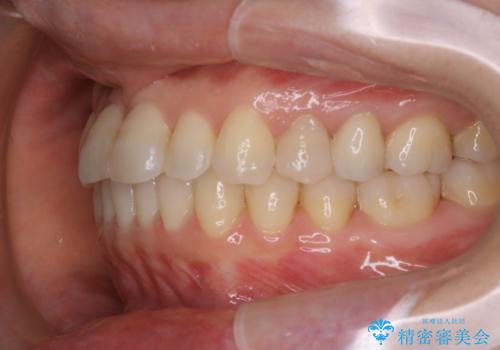

矯正治療とセラミック治療が終了後のPMTC

- 矯正治療とセラミック治療の総合治療が終了したため、クリーニングをしっかりとしてからメンテナンスに入りたいとのことでした。PMTC30分コースを行いました。

矯正治療が終わり、せっかくきれいになった歯並びも、虫歯・歯周病などになってしまっては元も子もありません。

矯正治療やセラミックなどによる被せ物の治療終了のタイミングではクリーニングを行い、汚れや着色の除去、歯と歯の間・歯と歯肉との境目などのケアをしっかりすることをおすすめしています。

ご自身での歯ブラシ・セルフケアを行うと同時に、定期的なクリーニング(PMTC)を行うことで、いつまでも健康な歯を保つことができます。